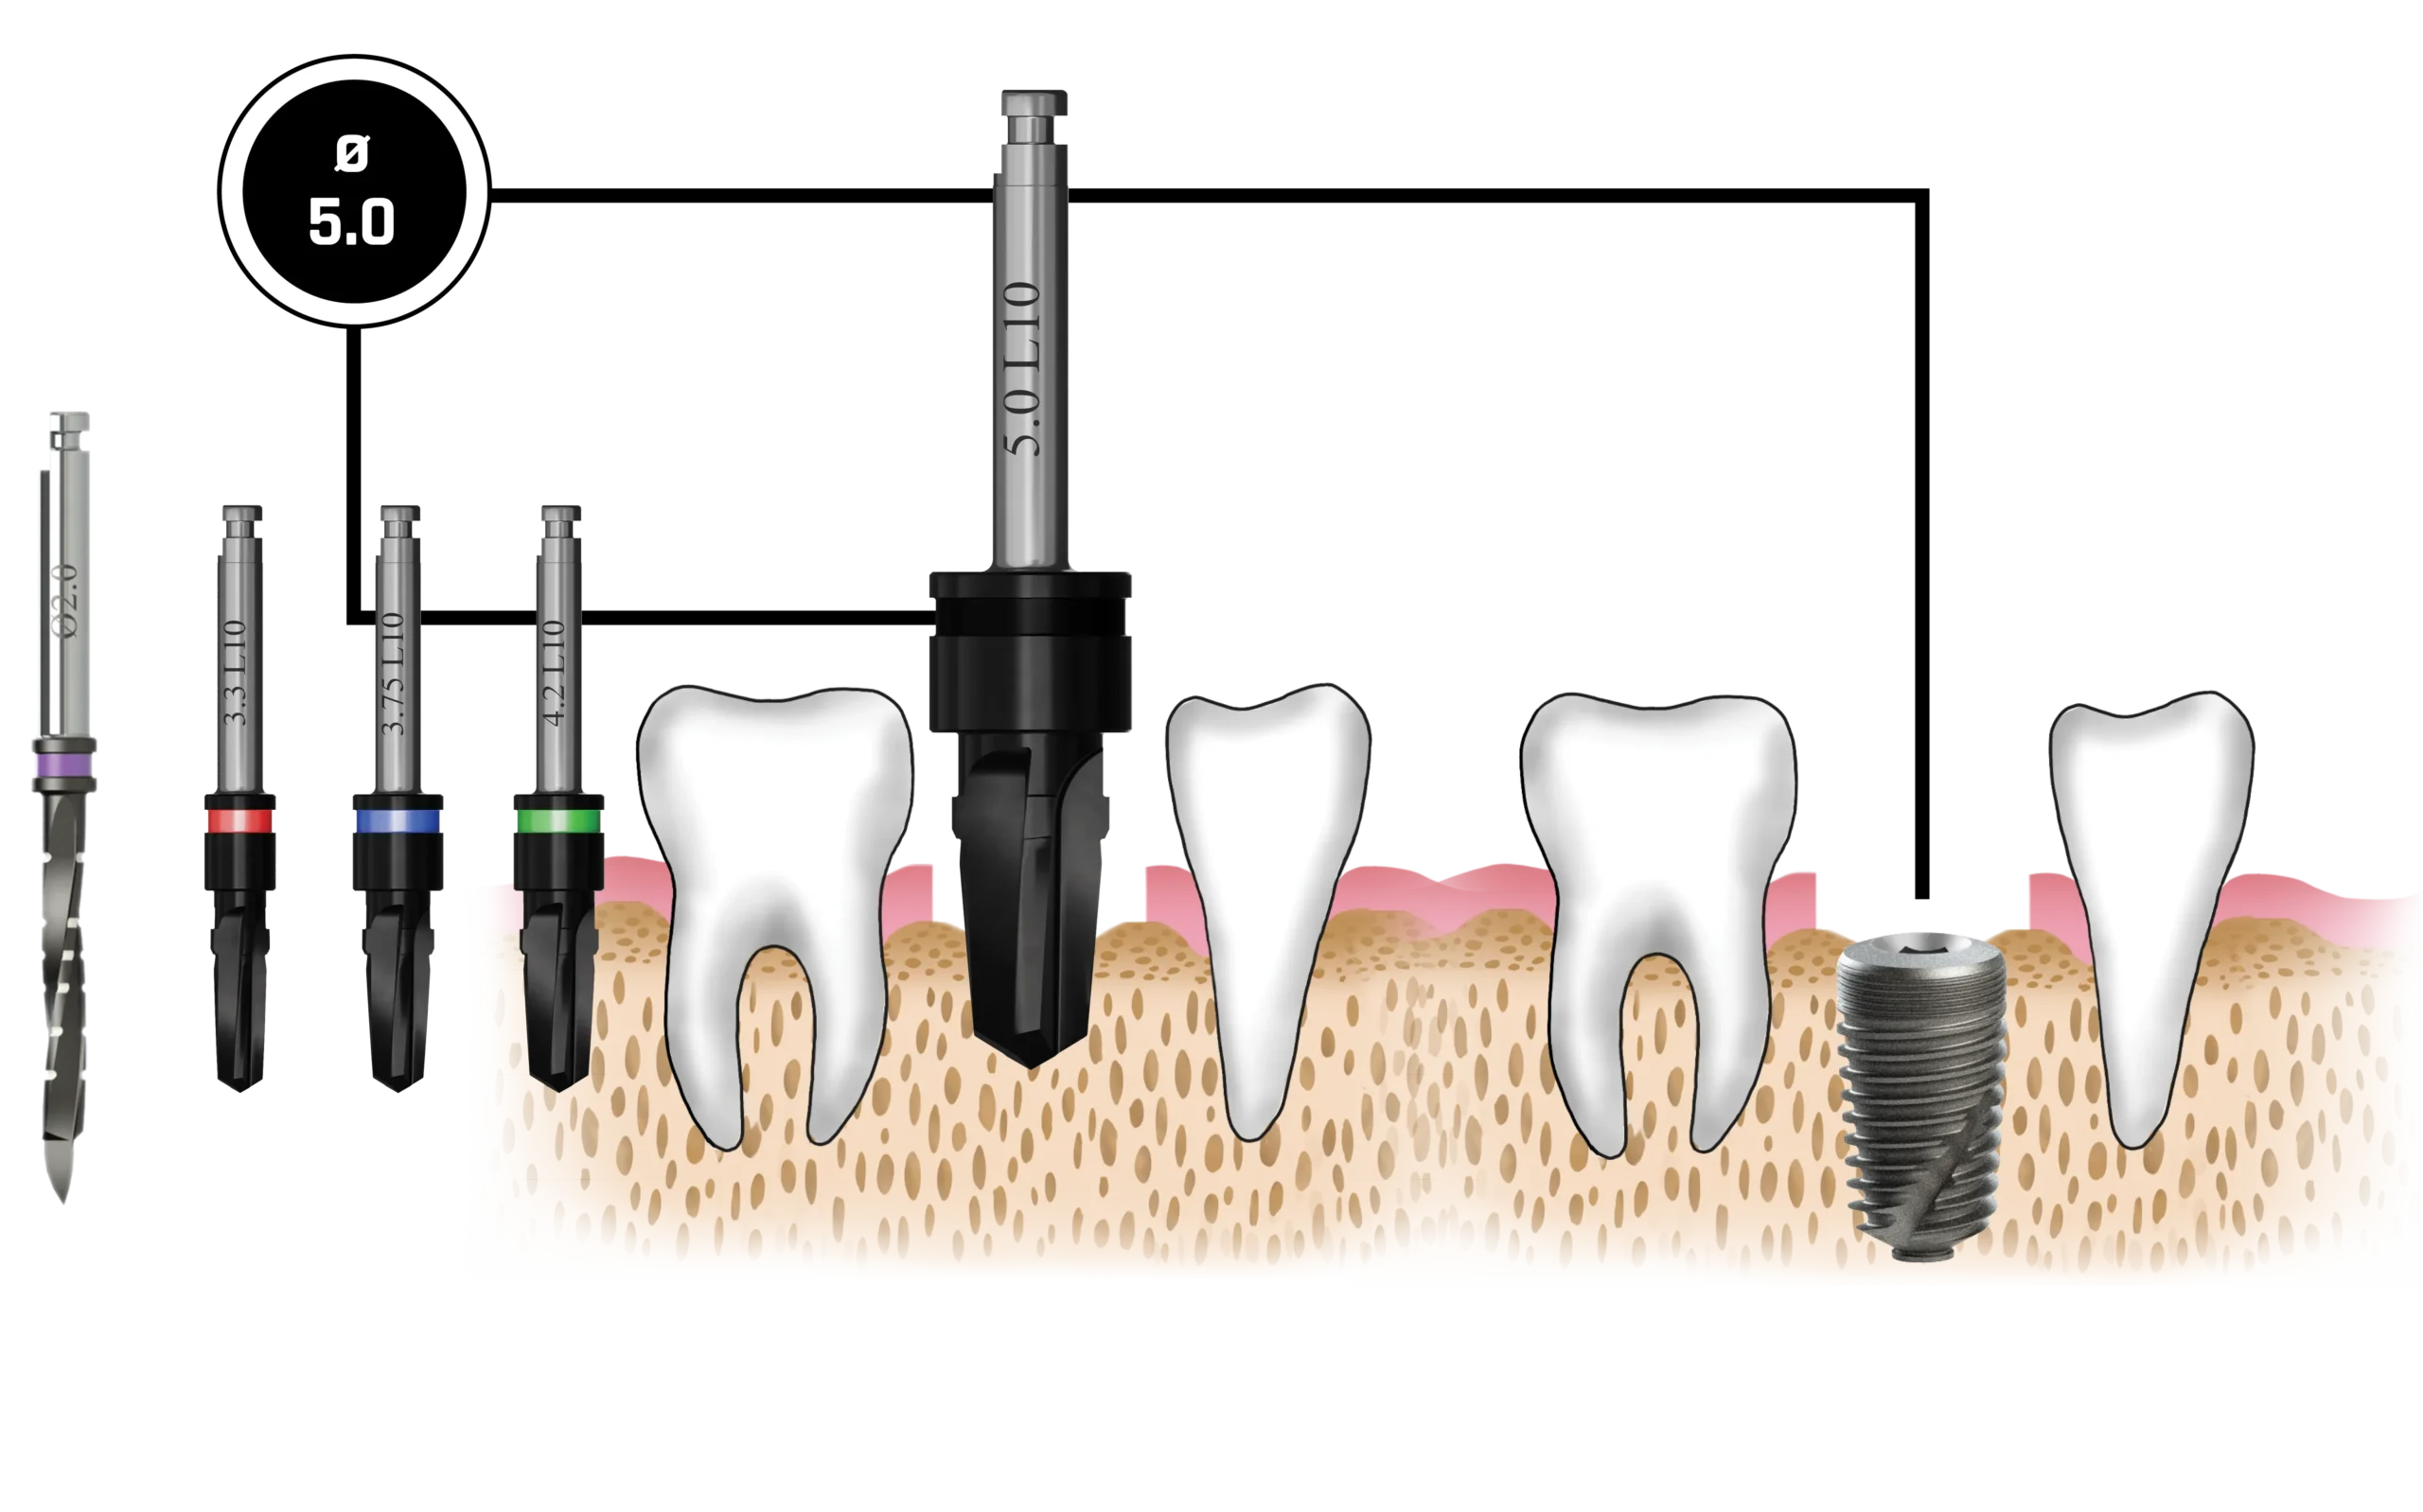

Quy trình mũi khoan

Nên sử dụng mũi khoan mồi 2.0 mm cho tất cả các đường kính implant. Các implant có đường kính 3.0 mm và 3.3 mm (Dòng Hẹp – Narrow Line) cùng với implant đường kính 3.75 mm (Dòng Tiêu Chuẩn – Standard Platform) nên được đặt ngang mức đỉnh xương. Các implant đường kính 4.2 mm, 5.0 mm và 6.0 mm (Dòng Tiêu Chuẩn – Standard Platform) có thể được đặt dưới mức đỉnh xương